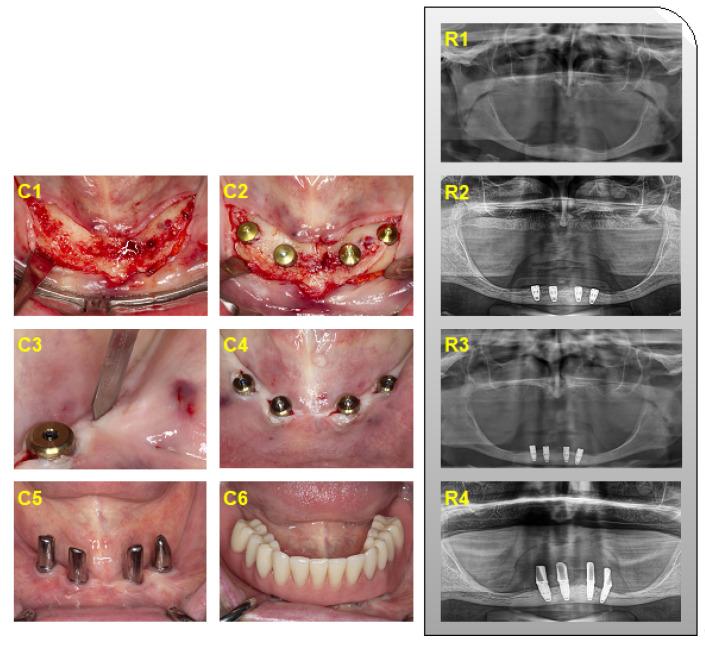

Iliac crest autografts can compensate for severe mandibular atrophy before implant placement. However, the implant success in the augmented bone is not entirely predictable. Here we performed a retrospective cohort study to determine the success and related parameters of implants placed in augmented bone and pristine bone for up to 11 years.

We analyzed 18 patients where 72 implants were placed six months after iliac crest transplantation and 19 patients where 76 implants were placed in pristine bone. The primary endpoint was implant loss. Secondary endpoints were the implant success, peri-implant bone loss, and the clinical parameters related to peri-implantitis. Moreover, we evaluated the oral-health-related quality of life (OHIP).

Within a mean follow-up of 5.8 ± 2.2 and 7.6 ± 2.8 years, six but no implants were lost when placed in augmented and pristine bone, respectively. Among those implants remaining in situ, 58% and 68% were rated as implant success ( = 0.09). A total of 11% and 16% of the implants placed in the augmented and the pristine bone were identified as peri-implantitis ( = 0.08). Bone loss was similar in both groups, with a mean of 2.95 ± 1.72 mm and 2.44 ± 0.76 mm. The mean OHIP scores were 16.36 ± 13.76 and 8.78 ± 7.21 in the augmentation and the control group, respectively ( = 0.35).

Implants placed in iliac crest autografts have a higher risk for implant loss and lower implant success rates compared to those placed in the pristine bone.